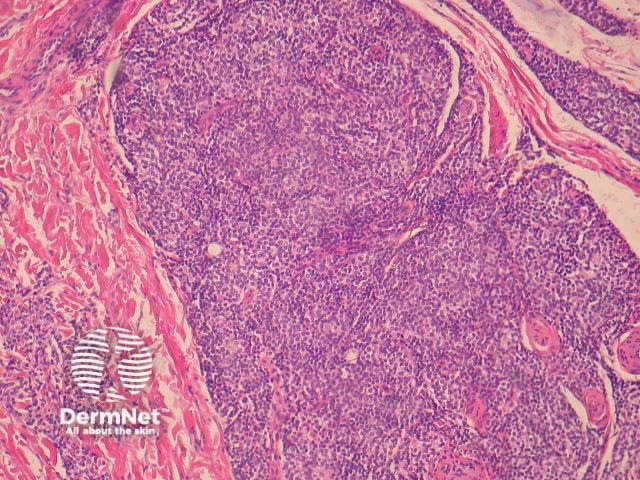

Histologically, indolent CD8+ lymphoid proliferations are characterised by a dense dermal infiltrate of non-epidermotropic, medium sized pleomorphic lymphocytes. These form a dense mass in the dermis and may involve subcutaneous tissues (figures 1-5).